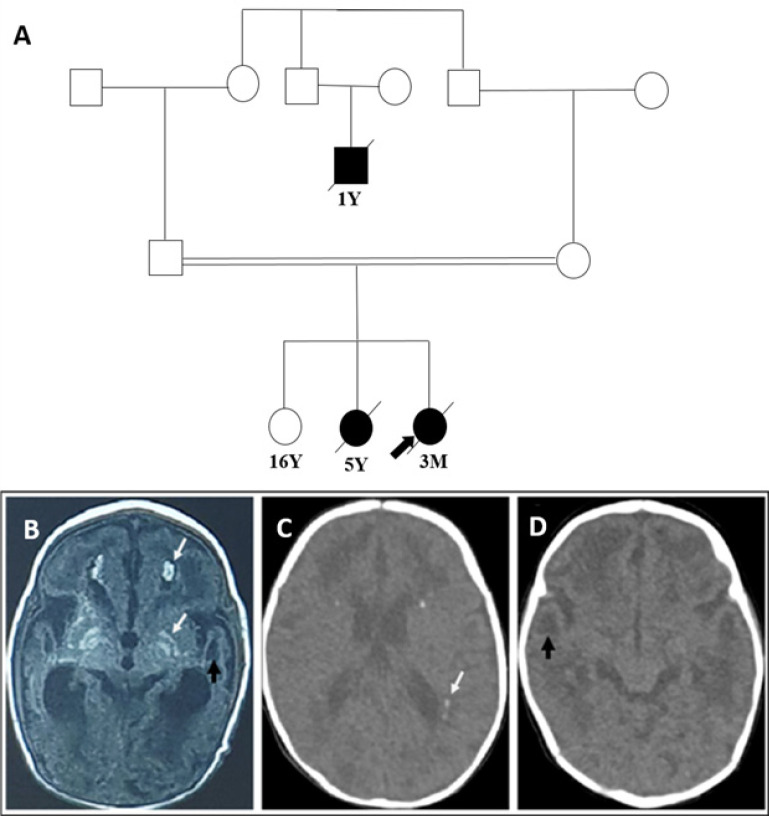

Materials & methods: The present study described two affected siblings from an Iranian family whose phenotypes overlap with intrauterine infections. They had almost similar presentations, including developmental delay, microcephaly, no fix and follow epileptic seizures and the same pattern of brain CT scan involvements. Following clinical and paraclinical assessments, whole-exome sequencing was employed to determine the disease-causing variant, and subsequently, PCR-Sanger sequencing was performed to indicate the segregation pattern of the candidate variant in family members.

Results: Genetic analysis revealed a novel homozygous missense variant (c.461A>C; p.D154A) in the TREX1 gene in affected family members. Sanger sequencing of other family members showed the expected zygosities.